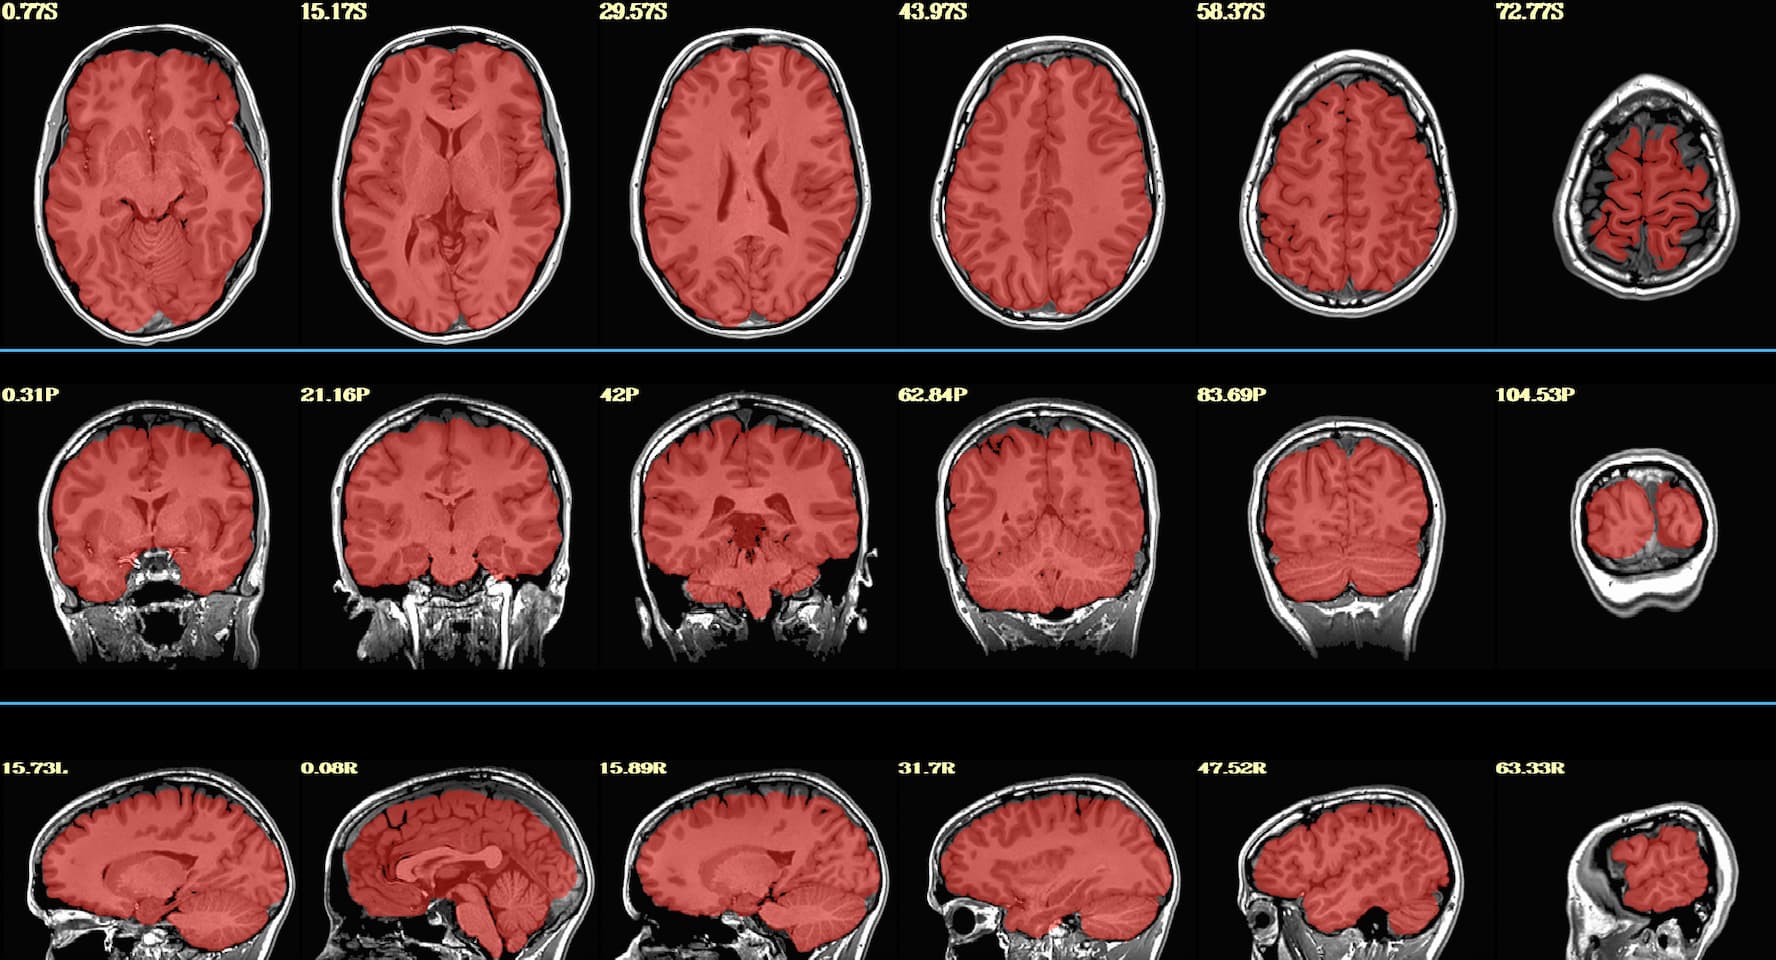

Hello, we have a few participants where parts of their brain got stripped along with their skull (see example below). They were originally processed on sswarper, and sswarper2 / push to edge both made things worse.

We ended up re-running sswarper2 locally using AFNI version 26.0.05. With this, the original and warped anatomical look ok in afni, but the jpgs in sswaper2 and QC html files still look aggressively stripped. What is the recommended procedure for attempting to fix this? Thank you!